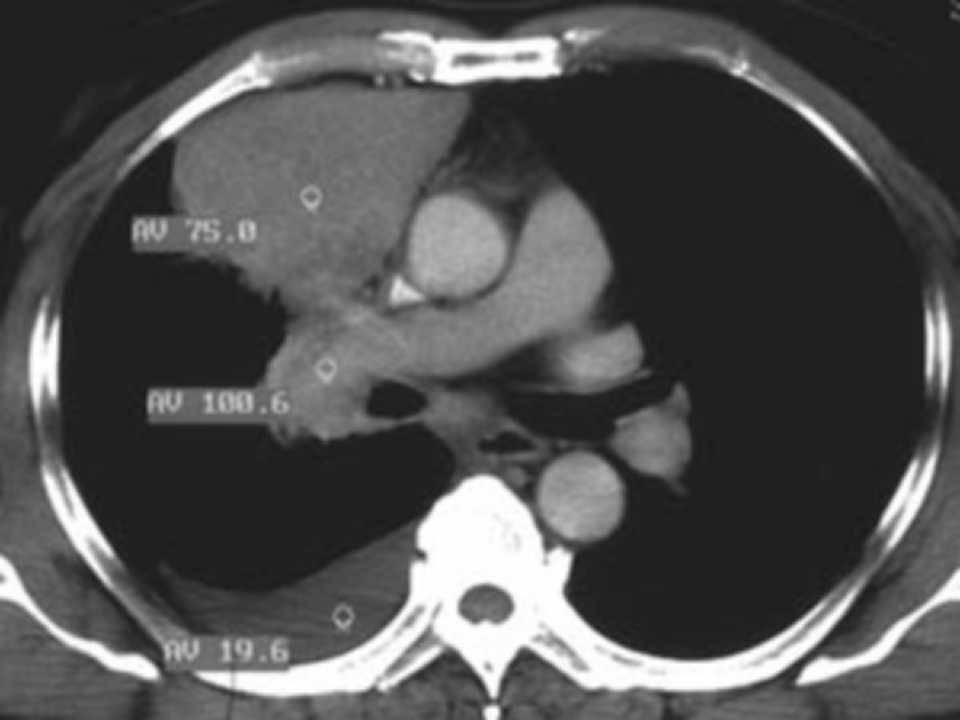

肺癌影像学表现